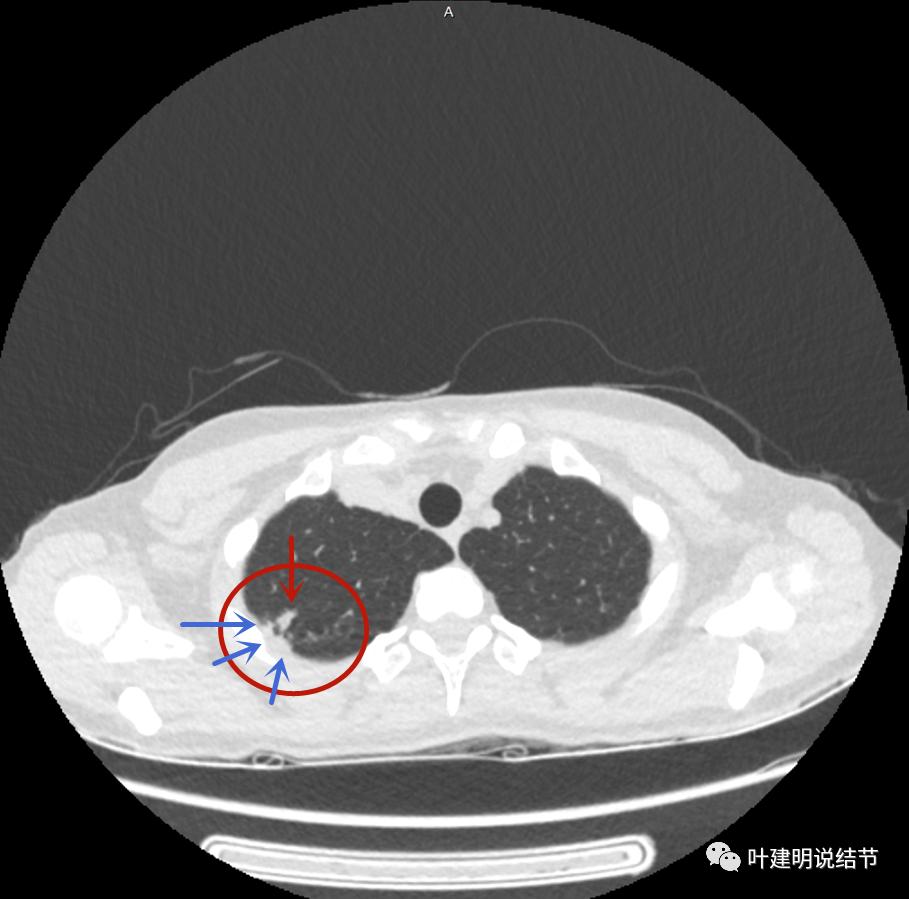

主病灶边界较清(红色箭头),实性部分密度过高(粉色箭头),病灶边缘向内凹,缺乏膨胀性(桔色箭头),病灶有空腔(黄色箭头)

邻近胸膜有增厚(蓝色箭头),主病灶的壁密度过高且整个壁密度都高(粉色箭头),旁边有磨玻璃影,散且模糊(砖色箭头)。内壁不均质(此不舒服)

邻近胸膜有增厚(蓝色箭头),主病灶囊壁密度过高(粉色箭头),内部有突起(细红色箭头),旁边有磨玻璃影,散且模糊(砖色箭头),中间有空腔,内壁有些区域又是光滑的